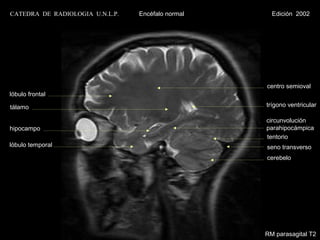

CATEDRA DE RADIOLOGIA U.N.L.P.   Encéfalo normal     Edición 2002

centro semioval

lóbulo frontal

tálamo                                             trígono ventricular

circunvolución

hipocampo                                          parahipocámpica

tentorio

lóbulo temporal                                    seno transverso

cerebelo

RM parasagital T2